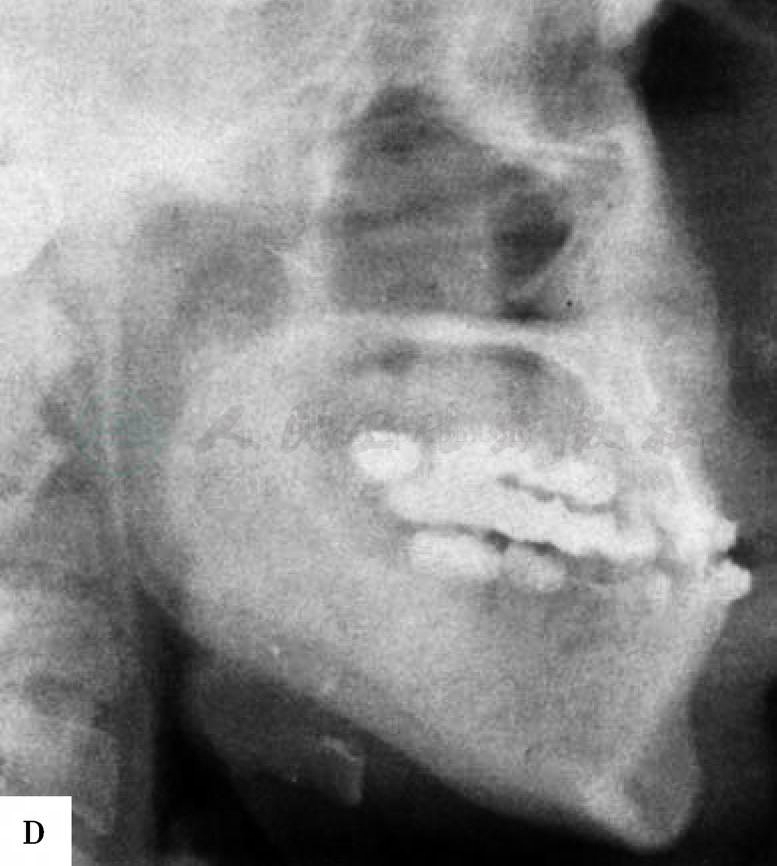

图2 下颌前突畸形患者,采用下颌体部台阶状截骨术进行矫正。A-D,患者术前面像和颌骨X线片。